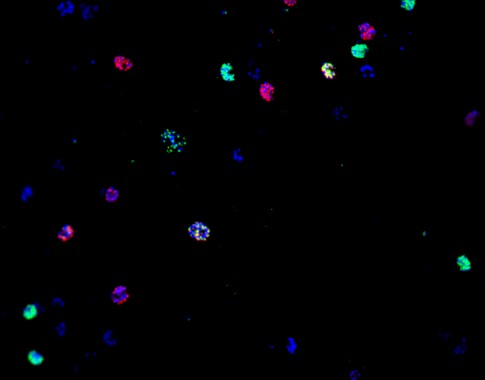

Expresión de la proteína CLAG3 en P. falciparum, detectada por inmunofluorescencia. (Foto: Miró et al, 2019)

Previamente, Cortés y su equipo habían demostrado que cambios en la expresión de clag3 resultaban en cambios en la permeabilidad de PSAC y una mayor resistencia a compuestos tóxicos para el parásito. En este estudio, el equipo se preguntó si otros antimaláricos necesitan la expresión de clag3 para actuar sobre su diana intracelular y que por lo tanto pudieran estar sujetos a resistencias por mecanismos epigenéticos.